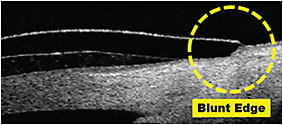

When patients have complaints of contact lens discomfort and the slit lamp findings are inconclusive, we often question the quality of the lens edge. Having the patient fixate off-center during OCT image capture allows us to view the edge profile in cross section. Figure 8 illustrates a poorly manufactured lens edge, resulting in a blunt tip with acute points that could affect patient comfort. By comparison, Figure 9 shows an optimally finished edge with a well-rounded tip that is conducive to a smooth landing and comfortable fitting relationship.

Figure 8. A poorly manufactured lens edge, resulting in a blunt tip with acute points.